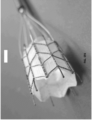

- An endograft system further comprises a delivery catheter with an operable tubular sheath capable of housing a folded or compressed endograft implant prior to deployment and capable of retracting or otherwise opening in at least its proximal end to allow implant deployment.

- the sheath is sized and configured to allow its placement via a peripheral arteriotomy site, and is of appropriate length to allow its advancement into, for example, the aortic valve annulus, ascending aorta, aortic arch, and thoracic or abdominal aorta, as required for a specific application. Sheath movement is provided in a novel manner by manual actuation and/or automatic actuation.

- a sealable vascular endograft system for placement in a vascular defect comprising an elongated main implant delivery catheter with an external end and an internal end for placement in a blood vessel with internal walls.

- the main implant delivery catheter further comprises a main implant delivery catheter sheath that may be openable or removable at the internal end and a main implant delivery catheter lumen containing within a compressed or folded endovascular implant.

- an endovascular implant comprises a non-elastic tubular implant body with an accommodating proximal end terminating in a proximal sealable circumferential collar that may be expanded by the operator to achieve a fluid-tight seal between the proximal sealable circumferential collar and the internal walls of the blood vessel proximal to the vascular defect.

- an endovascular implant may further comprise a non-elastic tubular implant body with an accommodating distal end terminating in a distal sealable circumferential collar controlled by a distal variable sealing device, which may be expanded by the operator to achieve a fluid-tight seal between the distal sealable circumferential collar and the internal walls of the blood vessel distal to the vascular defect.